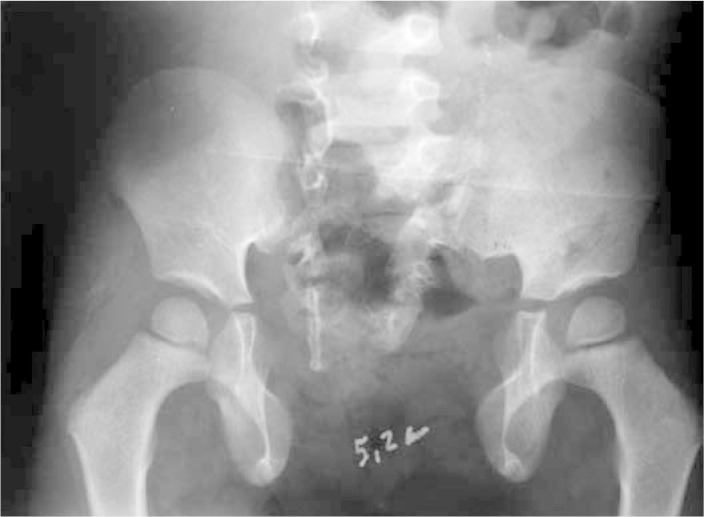

The second patient was referred at the age of five years, for correction of epispadia and for pelvic osteotomy to be performed. Closure of the cloacal exstrophy had already been performed at another hospital. Before the operation, the patient presented pubic diastasis of 5.2 cm (Figure 6)

Figure 6.

Preoperative radiograph on patient with cloacal exstrophy, showing public diastasis of 5.2 cm.

In January 2009, i.e. two years after the operation, it was seen that the patient had lost some of the reduction of the symphysis, to 3.6 cm (Figure 9). The gait projection angle before the operation was 35°, and this was reduced to 15°. Before the operation, the patient's gait presented external rotation, which was found at the postoperative assessment to have been corrected. There was no recurrence or complications from the urological abnormalities

Figure 9.

Pelvic radiograph produced one year after the operation, showing a diastasis of 3.6 cm.